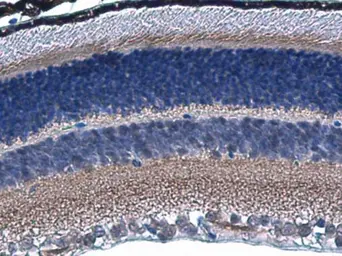

HCN1 antibody detects HCN1 protein in mouse retina by immunohistochemical analysis.

Sample: Paraffin-embedded mouse retina.

HCN1 antibody (GTX131334) diluted at 1:800.

Antigen Retrieval: Citrate buffer, pH 6.0, 15 min